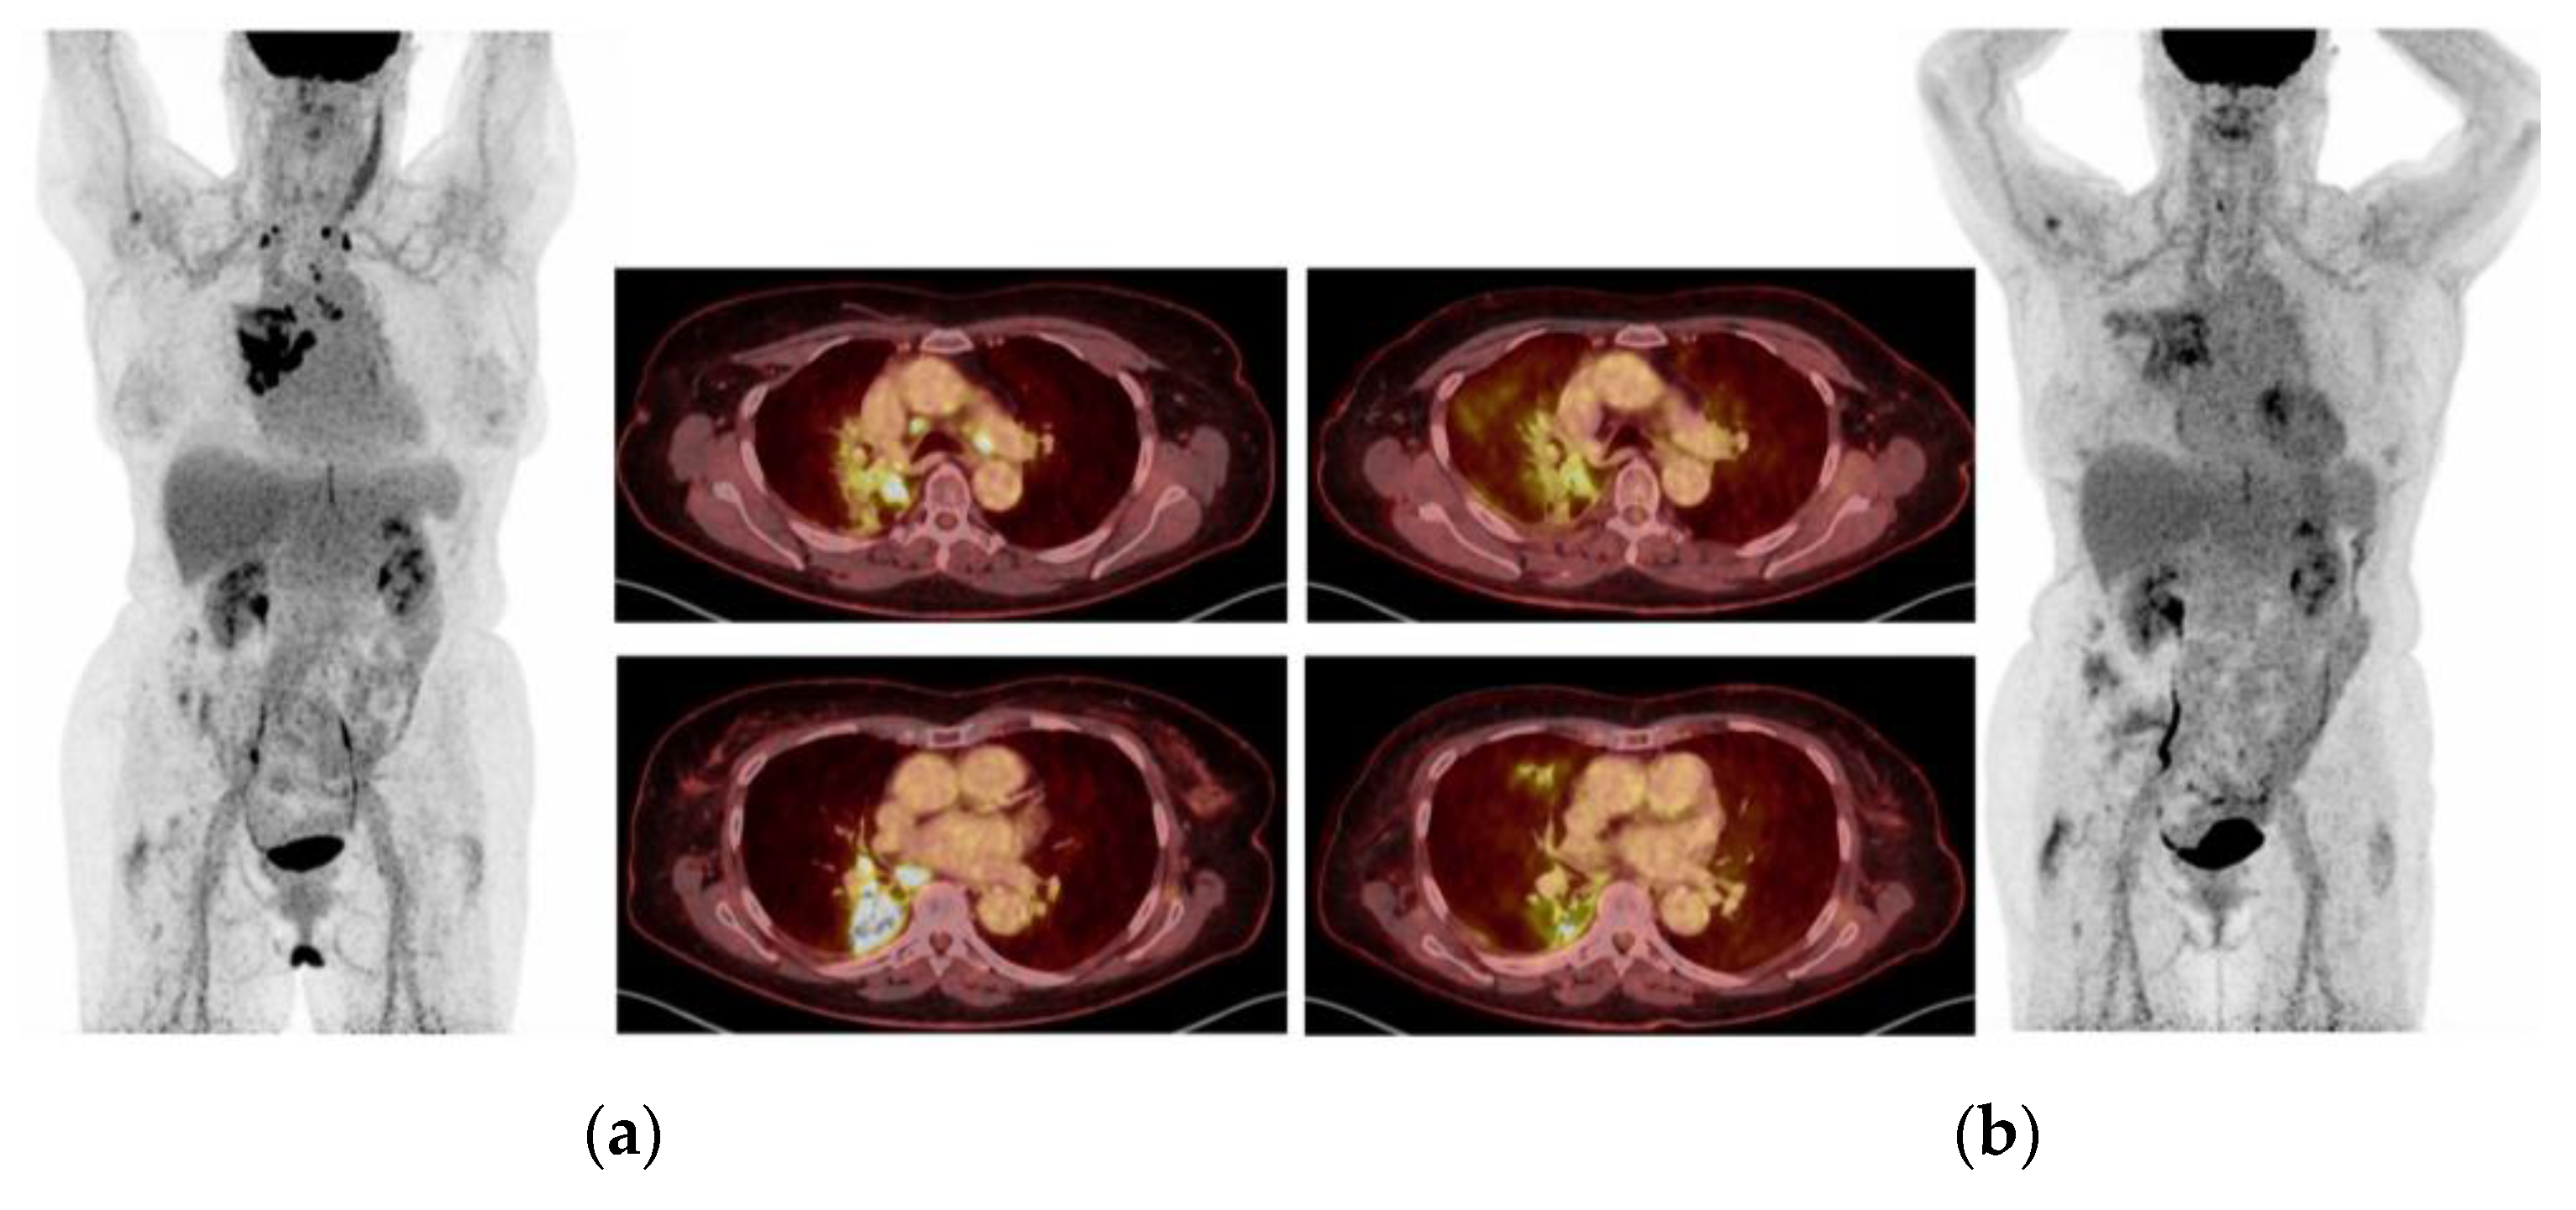

2.5. Case 5: Efficacy of Crizotinib-Osimertinib in EGFRm+ NSCLC Patient Acquiring High-Level MET Amplification after 26 Months of Treatment with Osimertinib